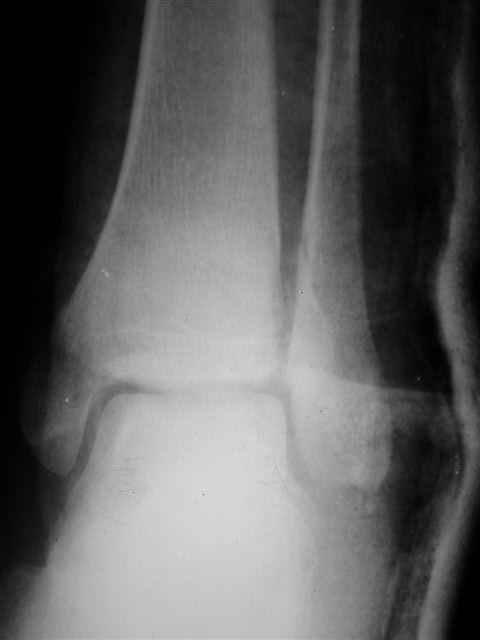

Я предупреждал, что ничего сверхъестественного. Каюсь, что одна из спиц прошла несколько дальше, чем нужно было, но главное - перелом стабилизирован и больной работает суставом в полном объёме, несмотря на представленную раннее травму коленного сустава.